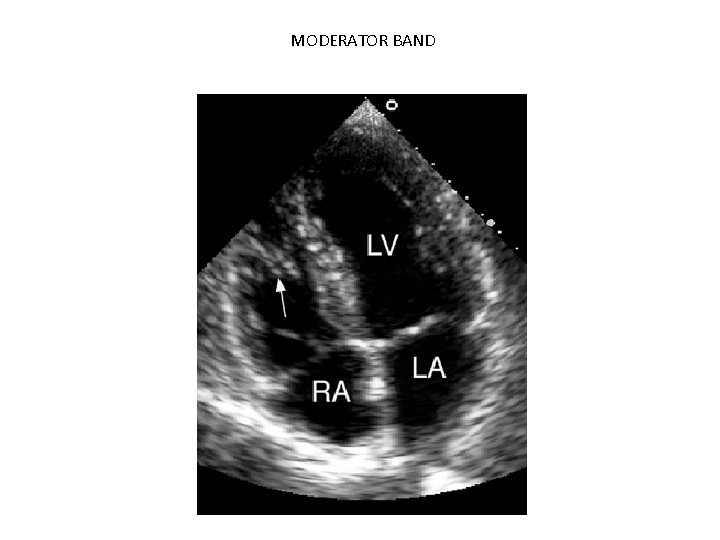

MODERATOR BAND